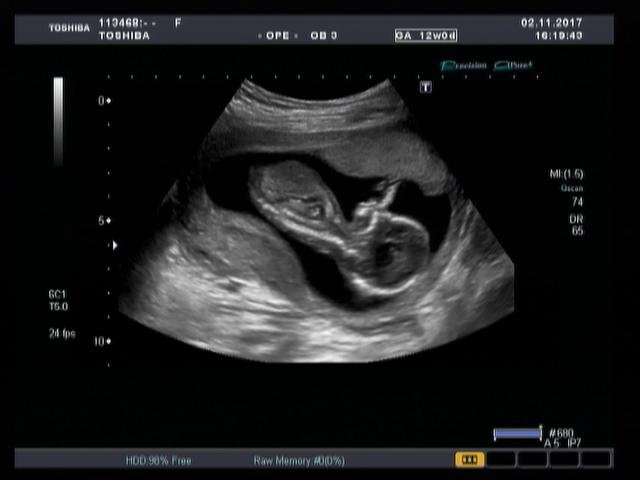

Precision Imaging (Прецизионная визуализация) ультразвуковой системы Aplio позволяют получать более реалистичные изображения и обеспечивает высокую степень послойной дифференцировки тканевых структур и анатомическую точность в визуализации деталей.

Функция автоматического измерения толщины воротникового пространства (Auto NT measurement) представляет собой инструмент для оценки размера воротниковой зоны плода, обеспечивающий превосходную воспроизводимость результатов. Эта функция позволяет проводить автоматические измерения и получать достоверные и воспроизводимые результаты при недостаточно четкой визуализации.